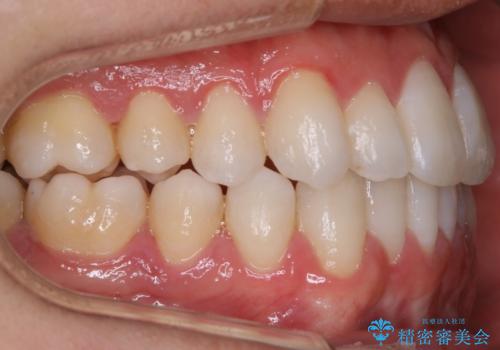

- 治療期間

- 2年

非抜歯での治療

抜歯をせずに歯のガタつきを治すためのスペースを作るために

①歯の遠心移動

②歯列弓の拡大

③IPR(歯を少し小さく削る)

この3つの方法を複合的に組み合わせて治療を行いました。

抜歯をせずとも笑った時の歯の見え方が劇的に変化していることが分かります。